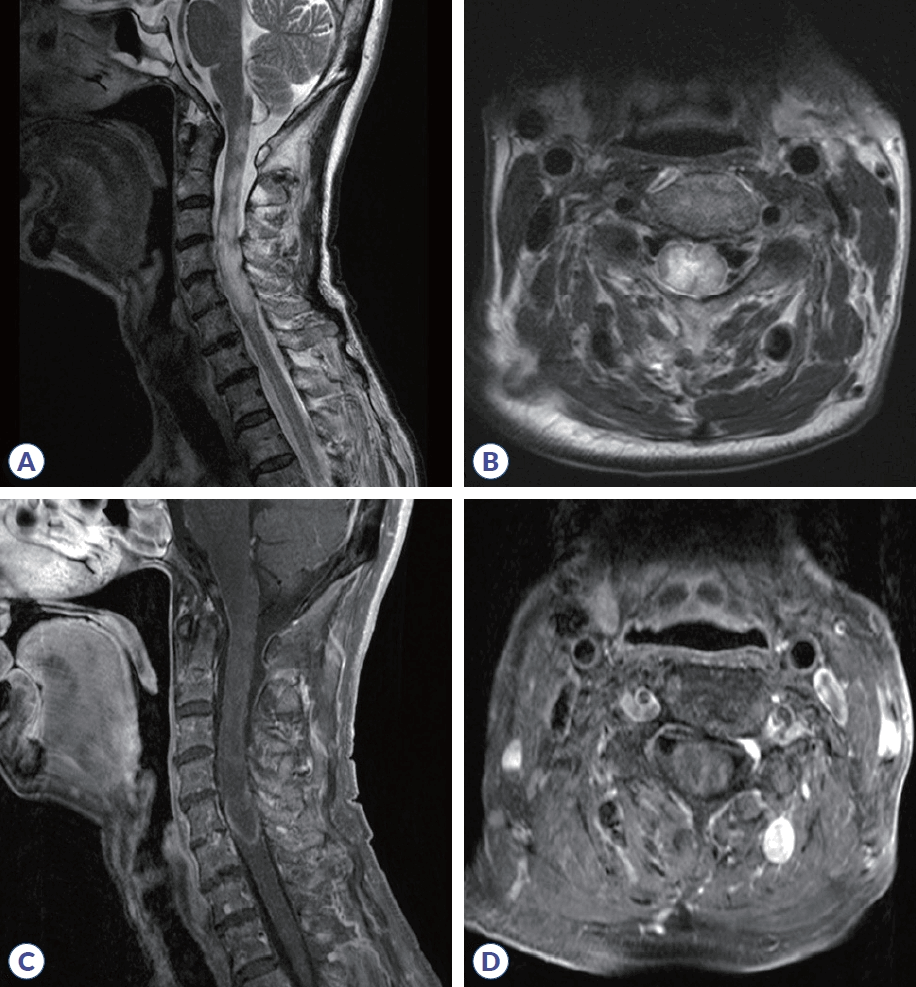

A 70-year-old female patient presented with a progressive arm sensory disturbance and severe bilateral leg weakness. Her medical history was notable for an asymptomatic right planum sphenoidale meningioma and chronic hepatitis B, for which she was taking antiviral medication. She had no other comorbidities. Four months before admission, she developed HZ on her right shoulder and neck, was treated with antiviral therapy. After a month, she experienced progressive fatigue, weakness, and hypesthesia in her right arm and shoulder, which spread to left arms. This was accompanied by stiffness and tonic spasms of both hands. Three months later, her weakness in both legs progressed rapidly.On admission, neurological examination showed normal alertness, language, and cranial nerve function. Sensory testing revealed hypesthesia involving all modalities below the C4 level, accompanied by right arm weakness (medical research council scale [MRC] 4/5-), and bilateral leg weakness (MRC 3/3), resulting in an expanded disability status scale (EDSS) score of 7.0. Deep tendon reflexes were brisk (+++) in the legs, with negative Babinski sign. Positive Lhermitte’s sign and truncal ataxia were present. While motor evoked potentials were normal, abnormal somatosensory evoked potentials in all limbs indicated a central sensory pathway deficit and electromyography suggested concurrent right brachial plexopathy. This suggests that sensory ataxia caused balance impairment and confounded clinical assessment of weakness. Cerebrospinal fluid (CSF) analysis showed 7 white blood cell count/μL (88% lymphocytes), protein 51 mg/dL (normal 8-43), and glucose 56.7 mg/dL (CSF/serum ratio 0.36). CSF VZV polymerase chain reaction (PCR) was negative, and the CSF FilmArray meningitis/encephalitis panel (Bio-Fire Diagnostics, Salt Lake City, UT, USA) meningitis/encephalitis panel was also negative. Following the prior clinical HZ diagnosis, CSF VZV IgG/immunoglobulin M (IgM) antibody titers were not obtained. Spinal magnetic resonance imaging (MRI) revealed cord swelling and T2 high-signal intensity from the C1-C6 level with inhomogeneous enhancement, consistent with longitudinally extensive transverse myelitis (LETM) (Fig. 1). Brain MRI was unremarkable aside from the known meningioma. Serologic testing revealed antinuclear antibody with a mitochondrial pattern at a titer of 1:160. All other tests were negative, including rheumatoid factor, anti-double-stranded DNA, antiphospholipid antibodies (including anticardiolipin IgG/IgM), antineutrophil cytoplasmic antibody, myelin oligodendrocyte glycoprotein antibody, and the paraneoplastic antibody panel. Anti-SS-A was borderline and anti-SS-B was negative. Cell-based assay (CBA) revealed a positive anti-AQP4 antibody (4+). Based on these findings, the patient was diagnosed with AQP4-positive NMOSD.The patient received high-dose intravenous methylprednisolone (1 g/day for 5 days) initially, but since there was no clinical improvement and weakness worsened slightly, intravenous immunoglobulin (IVIG) was subsequently administered for 5 days. Azathioprine (100 mg/day) was started for maintenance, with gabapentin and baclofen for symptom control. Her hypesthesia, ataxia, tonic spasms, and leg weakness partially improved (MRC 4/4). Serum anti-AQP4 antibody seroconverted to negative at 3 months and remained negative at the 7-month follow-up. Eight months post-hospitalization, due to hepatotoxicity and encephalopathy associated with chronic hepatitis B-related liver cirrhosis, azathioprine was discontinued, and maintenance therapy was switched to low-dose oral prednisolone. At the 1-year follow-up, her strength was maintained (MRC 4/5), but she remained wheelchair-dependent due to balance impairment, with an EDSS score of 6.0.

Figure 1.